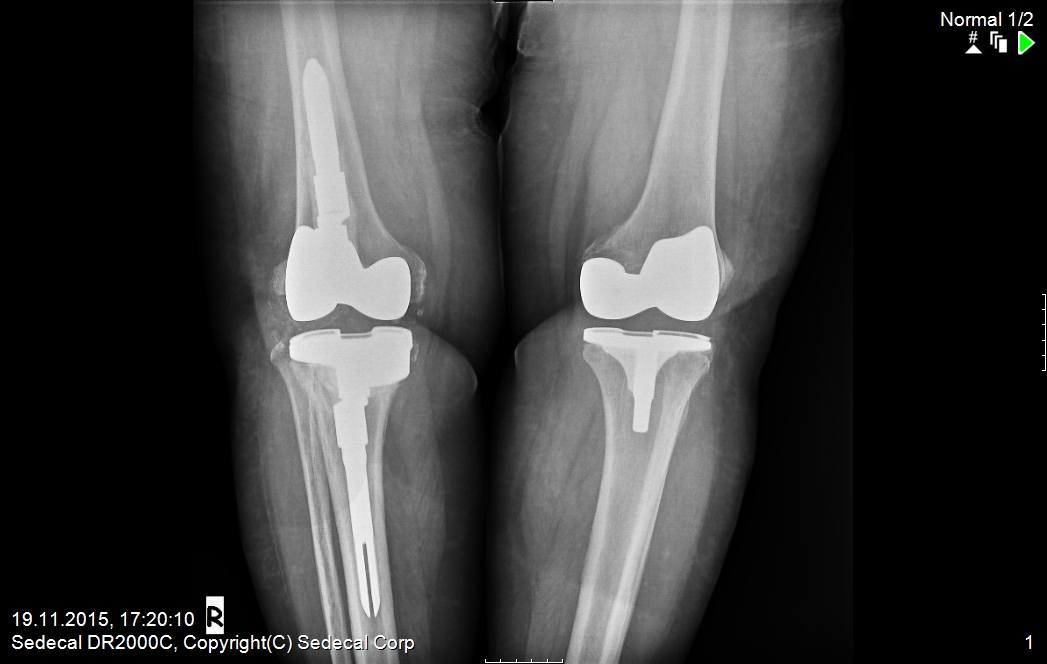

ameliyat sonrası yeni diz protezi 1

ameliyat sonrası yeni diz protezi 2